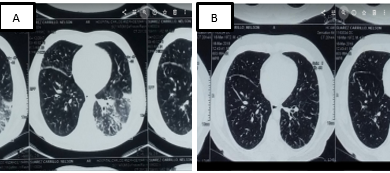

En la tomografía axial computarizada de alta resolución (TACAR) de tórax, se observaron áreas de consolidación, engrosamiento septal, bronquiectasias y ganglios mediastinales menores a 20 mm en nivel 4, 5 y 6. Figura 2.

Figura 2. A. TACAR 2017 Engrosamiento intersticial reticular nodular. Vidrio deslustrado mayor compromiso basal. B. TACAR 2019 Engrosamiento intersticial interlobulillar regresión de vidrio y consolidación. Fuente. Base de datos de la investigación.

Se decidió el inicio de tratamiento con prednisona a 40 mg por día, con disminución progresiva, tuvo una descompensación simple de diabetes que requirió ingreso a emergencia donde se incrementó la insulinización, por lo que se añadió al tratamiento micofenolato 1 500 mg por día, lo que permitió el destete progresivo de corticoides con buena respuesta clínica; mejoró el compromiso poliglandular, remisión de la dacrioadenitis, regresión del tamaño de glándulas parótidas, requerimiento mínimo de insulina, ha permanecido en tratamiento por dos años, al momento sin esteroides, continuó con micofenolato, en último control tomográfico de tórax se observó regresión de patrón en vidrio deslustrado y consolidación como se muestra en la figura 3.

La afectación torácica en la ER-IgG4 incluye al parénquima pulmonar, las vías respiratorias, el mediastino y la pleura20, las manifestaciones clínicas más frecuentes son tos seca, dolor torácico, fiebre, hemoptisis y disnea progresiva21; el paciente acude a emergencias por tos con hemoptoicos y febrículas. La tomografia pulmonar mostro un compromiso intersticial compatible con neumonía intersticial no específica con infiltrados retículo nodular y vidrio deslustrado. En el pulmón el compromiso puede darse de diversas maneras como un pseudo-tumor inflamatorio, neumonía intersticial (en forma de neumonía intersticial aguda, neumonía intersticial no específica, neumonía intersticial usual, neumonía organizada e incluso bronquiolitis obliterante), adenopatías, estenosis traqueobronquiales, derrame pleural e hipertensión pulmonar22. La ER-IgG4 debe considerarse como un diagnóstico diferencial de neumonía intersticial, si bien son pocos los casos publicados, la mayoría corresponde a neumonía intersticial no específica. Hasta un 50% de los casos puede ser asintomáticos al comienzo de la enfermedad22. Para la tomografía se han descrito diferentes tipos de patrones: lesiones nodulares solidas o masas, vidrio esmerilado, compromiso intersticio-alveolar (engrosamiento de septos inter e intralobulillares tipo panal de abejas y del intersticio peribroncovascular) y bronquiectasias21,22. Estas lesiones también pueden revertir con uso de esteroides, en este caso por la asociación de diabetes fue indispensable el uso de otro inmunosupresor (micofenolato) que permitió destete progresivo y regresión del vidrio deslustrado y áreas de consolidación.